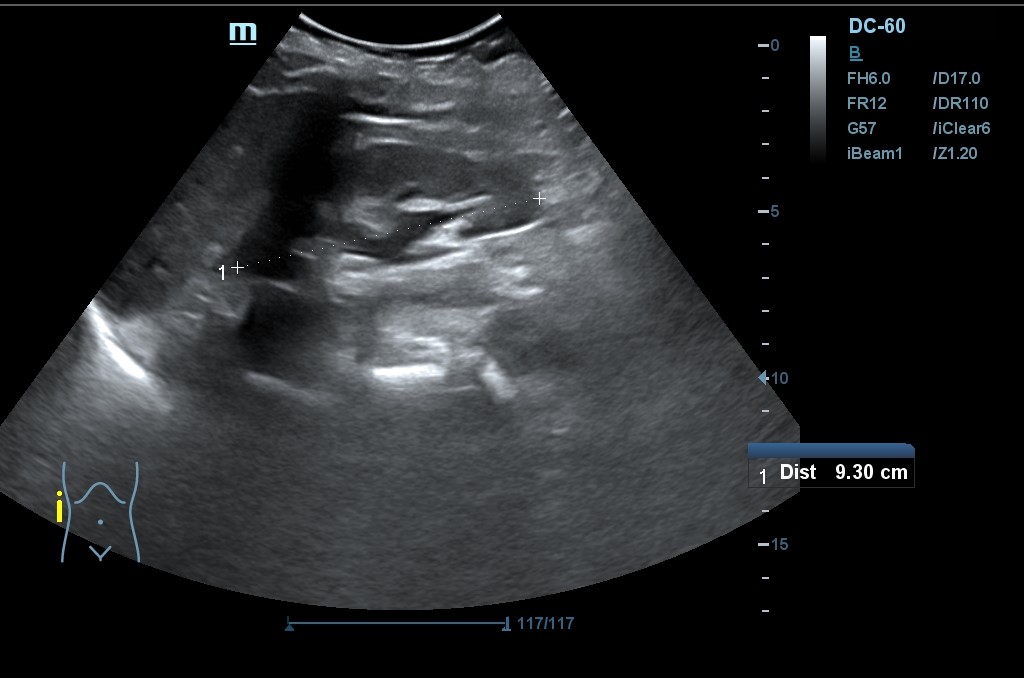

Hallazgo de lo que impresiona de nefromegalia izquierda de aproximadamente 14 cm con hidronefrosis bilateral grado 2.

Se realiza una nueva ecografía en la que se confirma la ascitis y persisten las alteraciones renales.

Tras la segunda ecografía se deriva a la paciente a la Unidad de Diagnóstico Rápido de Medicina Interna donde ingresa para completar estudio. Tras ecografía en la que informan de extenso tejido hipoecoico periaórtico y perirrenal izq. (nefromegalia izq.) con extensión nodular al mesenterio, se establece la sospecha de síndrome linfoproliferativo, así como en un TC posterior y que se confirma como Linfoma No Hodgkin mediante biopsia.